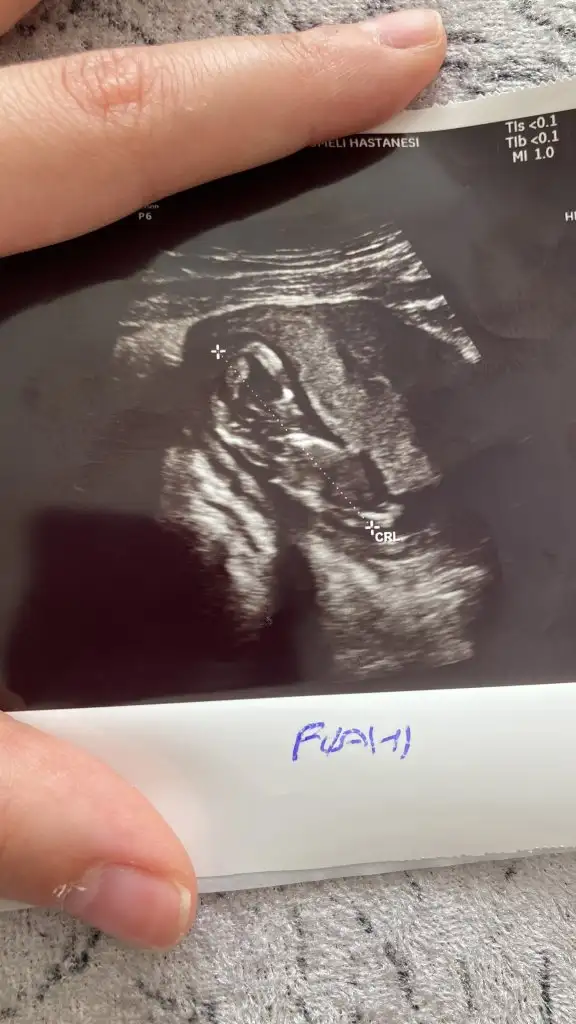

Benimkini de yorumlar mısın canım 10+1prenses gibi

paşa gibiPasha22 teyzemiz 10+1 günlük karından ultrason bize de tahmin de bulunur musun

Eki Görüntüle 3082017

net prensesMerhaba 13+3 karından çekılmıs ultrason. Tahmınınız nedir rica etsem?

net prenses